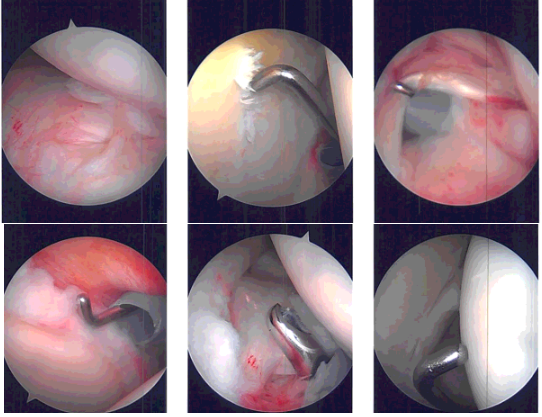

Intraoperative Arthroscopy Images

Entry to the anterior portal was made using a spinal needle through the rotator interval and cannula was inserted. Probe was used by examining the shoulder and found to have mild osteoarthritis, grade 1 to grade 2 osteoarthritis of the glenoid center.

There was partial tearing of the subscapularis, which was debrided. There was mild tendinitis of the biceps tendon and nothing was done for that. Complete rotator cuff tear was seen in the supraspinatus and Infraspinatus of the shoulder. There was fraying of the glenoid labrum, which was debrided using the shaver.

The examination of the shoulder was normal. The scope was entered through the anterior portal, findings. The scope was entered into the subacromial space.

Examination showed bursitis, which was debrided using the shaver. Big tear of the supraspinatus and infraspinatus was found. The tear was extending up to the biceps tendon.

The shoulder was thoroughly irrigated and drained. Closure was done using #3-0 Nylon, ABD and tape. The patient was extubated and moved to the recovery unit in a stable condition.